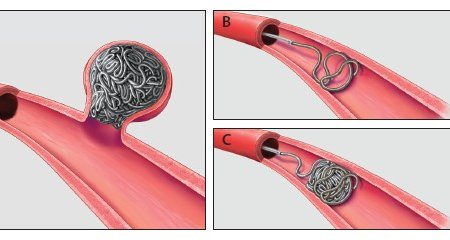

(Embolization)

هو يكون مثل اقفال النزيف بعد الحوادث واقفال بعض الاوعية الدموية باللفافات.